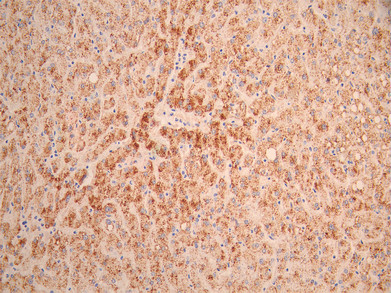

• IHC image of CSB-RA019483MA1HU diluted at 1:50 and staining in paraffin-embedded human liver cancer performed on a Leica BondTM system. After dewaxing and hydration, antigen retrieval was mediated by high pressure in a citrate buffer (pH 6.0). Section was blocked with 10% normal goat serum 30min at RT. Then primary antibody (1% BSA) was incubated at 4°C overnight. The primary is detected by a Anti-Human lgG, Fcy Fragment Specific labeled by HRP and visualized using 0.05% DAB.